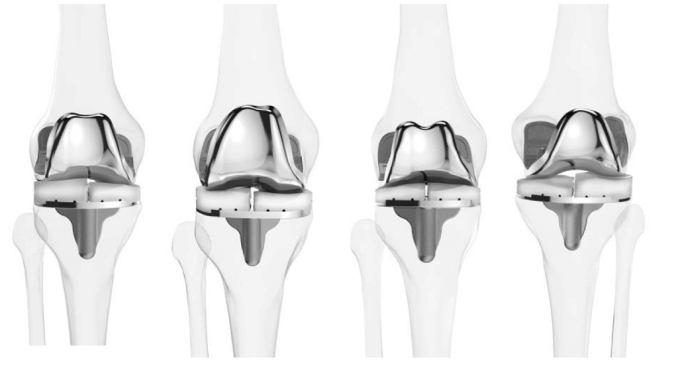

Εικόνα 3: Ολική αρθροπλαστική γόνατος

Διαφορετικοί τύποι εμφυτευμάτων γονάτου

Χρησιμοποιούνται διαφορετικοί τύποι εμφυτευμάτων γόνατος για την κάλυψη των εξατομικευμένων αναγκών του κάθε ασθενούς.

Εικόνα 4: Διαφορετικοί τύποι εμφυτευμάτων.